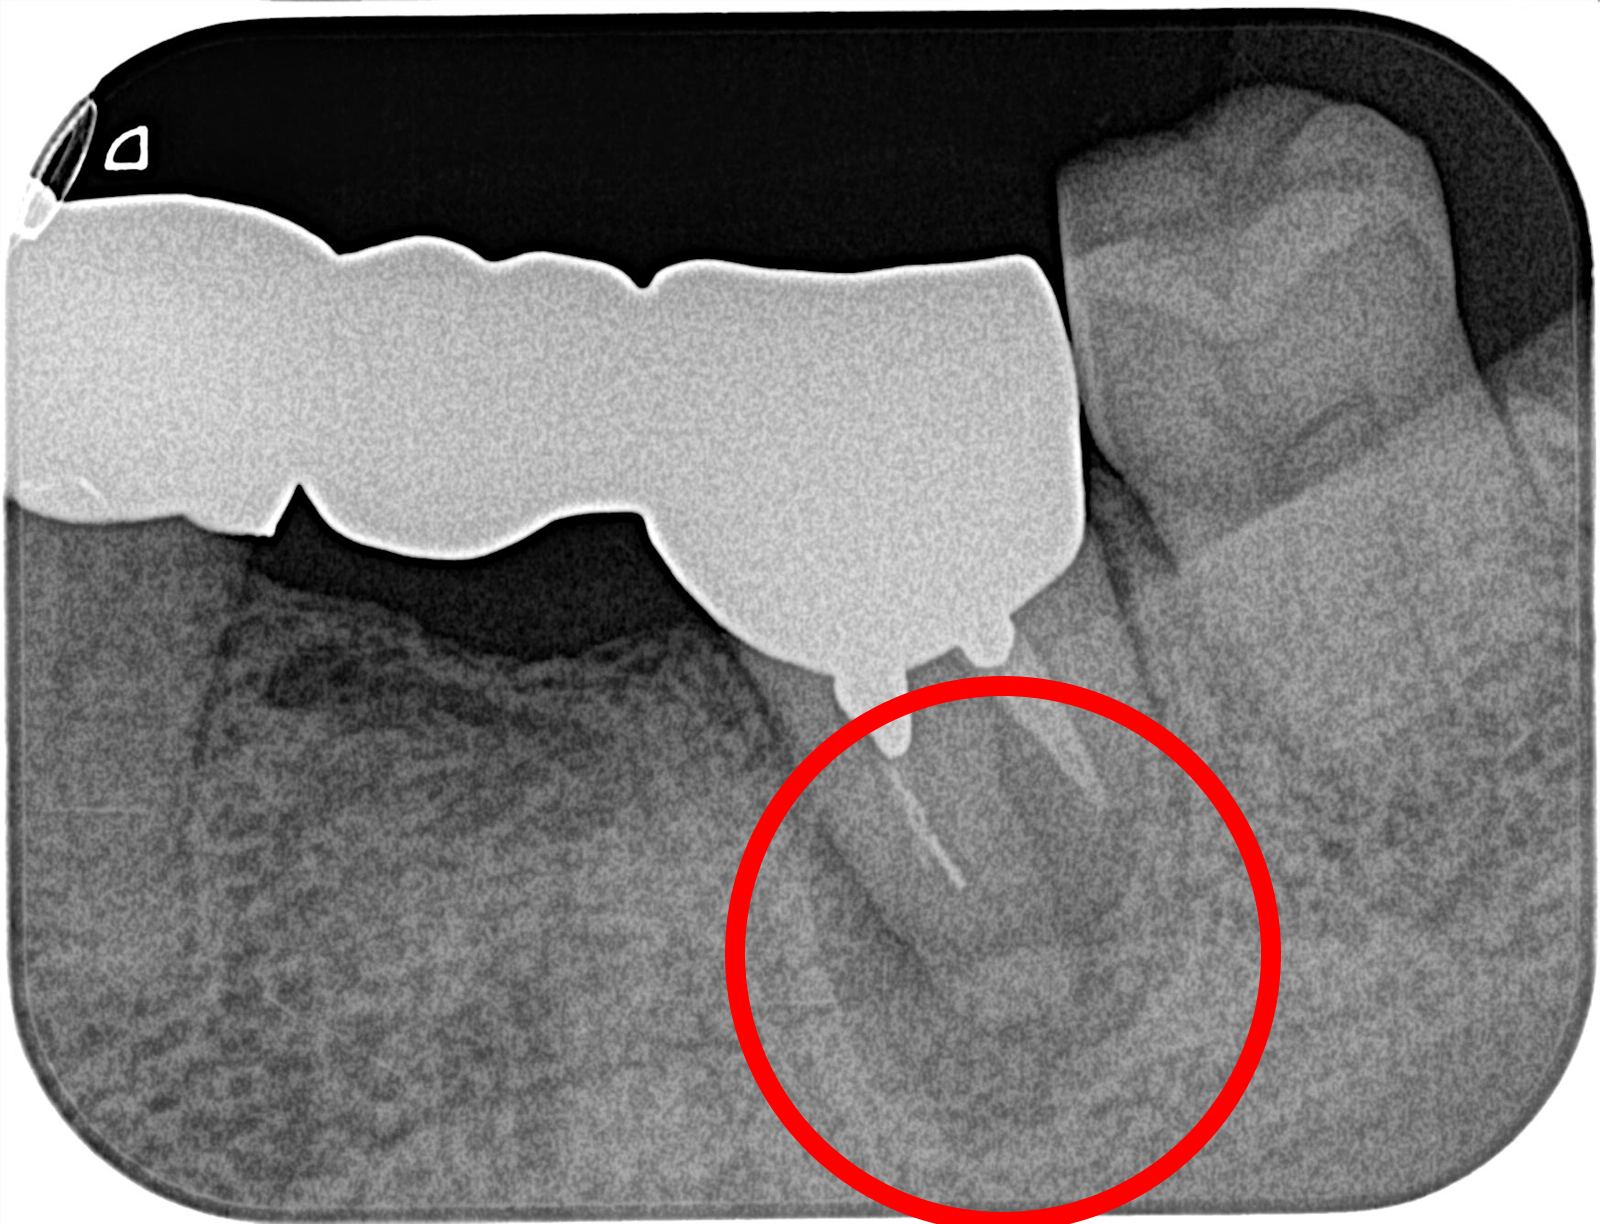

ブリッジを支える歯に過度な負荷がかかり、骨が吸収されたケース。

前医では抜歯と診断されたが、インプラントへの置き換えと根の治療により、歯を残すことができた。

歯根端切除術

根の先の病気も、抜歯せずに治す技術があります。通常の根管治療で治らない歯も、歯根端を外科的に処置することで、抜歯を回避できるケースがあります。

新海歯科医院では、歯科用CT、マイクロスコープ、ピエゾサージェリーなどの先進機器を駆使し、精密な歯根端切除術を実施。難易度の高い大臼歯の処置にも対応しており、埼玉県内トップクラスの症例実績を誇ります。